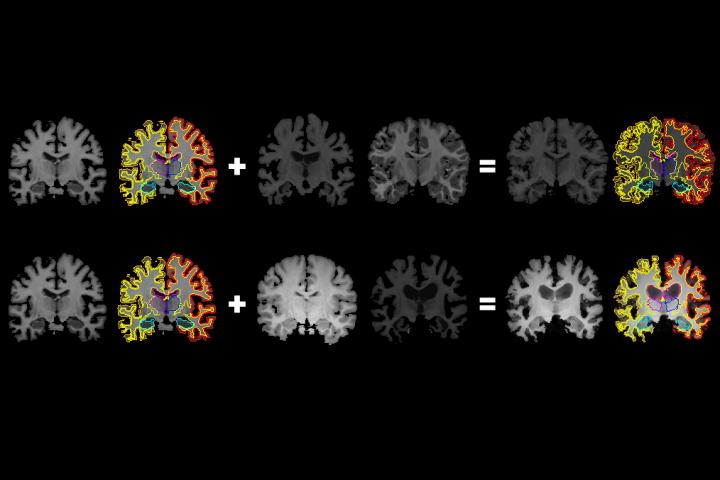

image: MIT researchers have developed a system that gleans far more labeled training data from unlabeled data, which could help machine-learning models better detect structural patterns in brain scans associated with neurological diseases. The system learns structural and appearance variations in unlabeled scans, and uses that information to shape and mold one labeled scan into thousands of new, distinct labeled scans.

The crux of the work is automatically generating data for the "image segmentation" process, which partitions an image into regions of pixels that are more meaningful and easier to analyze. To do so, the system uses a convolutional neural network (CNN), a machine-learning model that's become a powerhouse for image-processing tasks. The network analyzes a lot of unlabeled scans from different patients and different equipment to "learn" anatomical, brightness, and contrast variations. Then, it applies a random combination of those learned variations to a single labeled scan to synthesize new scans that are both realistic and accurately labeled. These newly synthesized scans are then fed into a different CNN that learns how to segment new images.

Instead, the researchers' system automatically learns how to synthesize realistic scans. The researchers trained their system on 100 unlabeled scans from real patients to compute spatial transformations -- anatomical correspondences from scan to scan. This generated as many "flow fields," which model how voxels move from one scan to another. Simultaneously, it computes intensity transformations, which capture appearance variations caused by image contrast, noise, and other factors.

In generating a new scan, the system applies a random flow field to the original labeled scan, which shifts around voxels until it structurally matches a real, unlabeled scan. Then, it overlays a random intensity transformation. Finally, the system maps the labels to the new structures, by following how the voxels moved in the flow field. In the end, the synthesized scans closely resemble the real, unlabeled scans -- but with accurate labels.